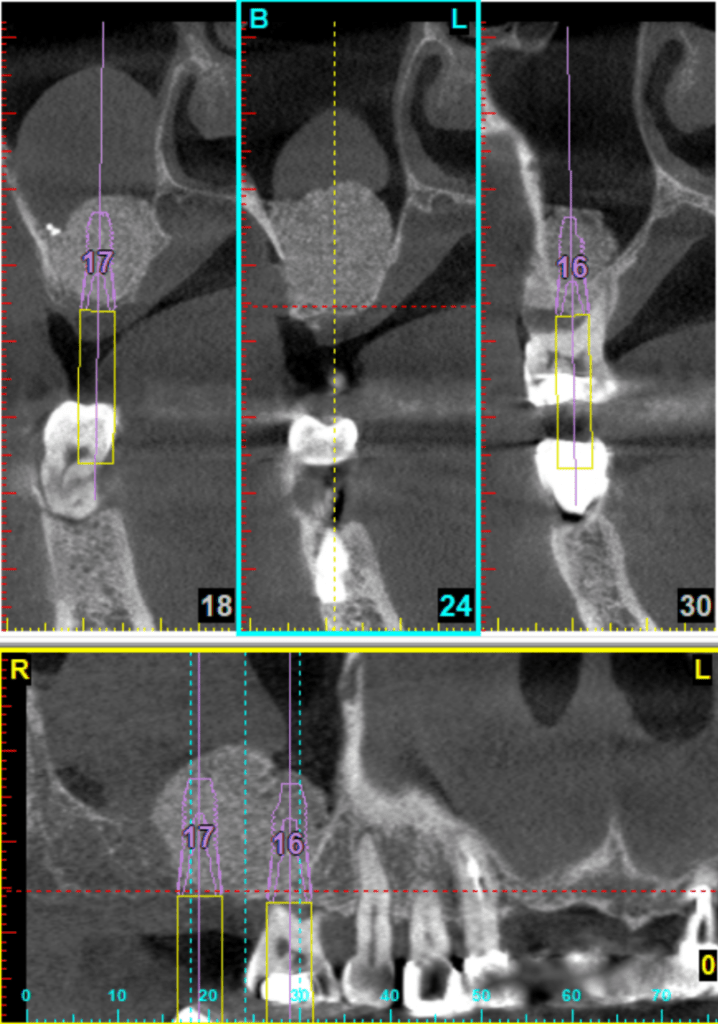

例如,一台開窗式鼻竇增高手術,能看好X光片與電腦斷層,腦中多次模擬手術過程,從切線設計、開窗位置、如何翻鼻竇膜、什麼位置有大血管、如何病人不在眼前,就可以先知道鼻竇內的高低起伏、器械需要準備哪些、有可能遇到什麼突發狀況、有什麼退路。這些都要想清楚。

十年來,我習慣每次開窗手術,都會親手繪製開窗所需要知道的刻度。骨頭高低起伏、牙根走向、血管位置、甚至有時候還會註記側窗骨質厚度等。當然也可以把電腦斷層的資料列印出來。

自己比較喜歡手繪,因為花個十分鐘,拿個鉛筆與橡皮擦,問自己一個問題:「什麼是最重要的資訊?」然後畫出最重要的幾個位置與刻度,相對位置與比例。透過親自手繪,比起列印斷層,來得更有臨場感,這也是手術前模擬的一環。

到手術當天,手繪圖就直接貼在旁邊,考試嘛,帶個小抄才不會答不出來啊~~

這也是我第一次嘗試在自然牙底下增高鼻竇,運氣不錯,自然牙底下的鼻竇質地平緩,只有顎側牙根稍有起伏,這也事先在3D模擬就知道,所以翻膜過程也不會感到驚訝與挫折。